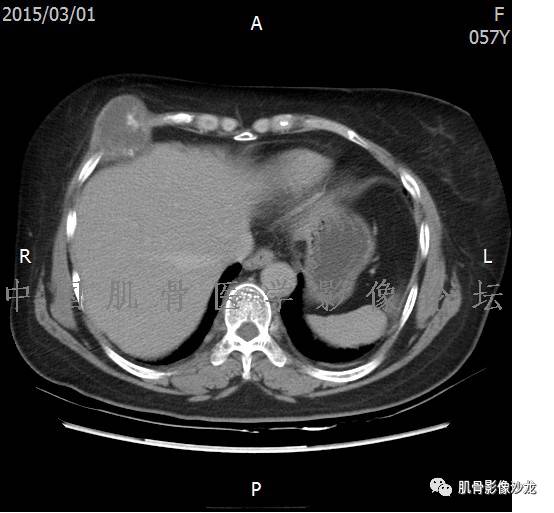

患者于2月前无明显诱因下出现腰骶部疼痛,夜间为重,逐渐加重伴左下肢麻木、疼痛,并有行走活动受限,在我院就诊,摄腰椎及骶髂部CT提示:腰椎骨质退变,腰3-4、4-5椎间盘膨出,骶髂关节炎。自用非甾体抗炎药无好转,再次来院就诊,门诊拟“骶髂关节炎”收住我科。病程无间歇性跛行,大小便正常。

专科检查:神清,脊柱无侧弯后凸畸形,椎体各节段无压、叩痛,双侧棘突旁无压痛,双侧骶髂关节压痛明显,左下肢放射痛,浅感觉较健侧减退,腰椎前屈后伸活动受限,膝、跟腱反射正常。

辅助检查:腰椎及骶髂部CT提示:腰椎骨质退变,腰3-4、4-5椎间盘膨出,骶髂关节炎。

雪舞 :第二例,位于骶骨,有骨质破坏并有软组织肿块,软组织肿块边界清

雪舞 :第二例挺难的,骨质破坏是溶骨性的,局部皮质中断,软组织肿块外缘光滑